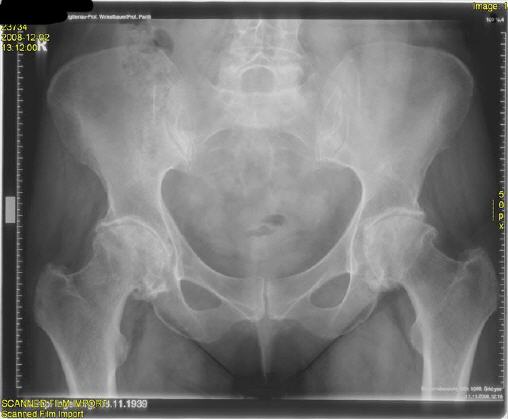

| schwere beidseitige Hüftgelenksarthrose - Coxarthrose |